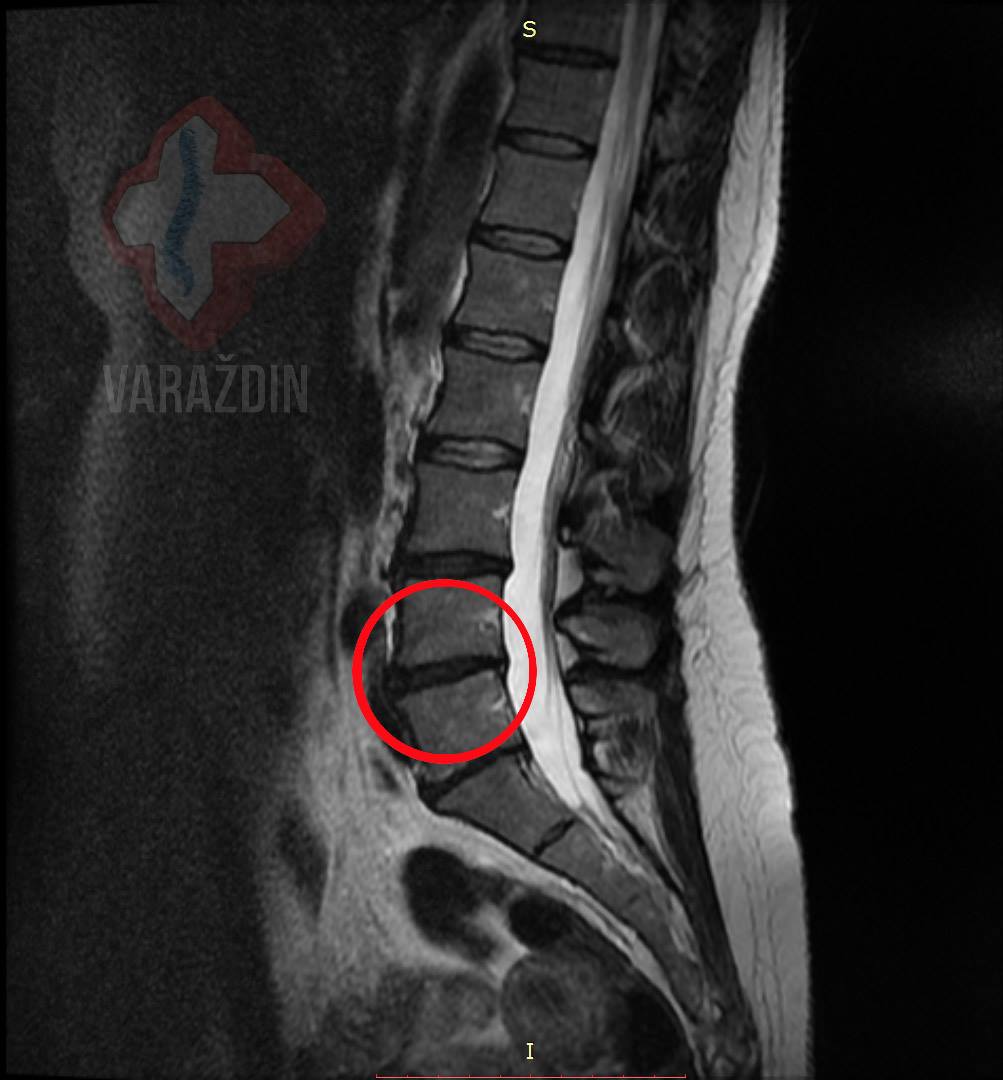

Primjer 5

Klijentica K.A. se javila uz vrlo snažnu bol u lumbalnom području

i lijevoj nozi. Bol je bila toliko jaka da je ležanje bilo moguće

jedino na desnom boku. Preporukom neurokirurga R.S. kreće na

dekompresijske tretmane u Nado centar zdravlja

Varaždin. Dekompresijski tretmani pokazali su se uspješnima,

obzirom da je klijentica nakon 8 tretmana uspješno prespavala

(što je do tada bilo potpuno nemoguće) noć na trbuhu. Rezultate

vidjeti možeti na slikama uz objavu. Hvala na preporuci

neurokirurgu R.S. i ukazanom povjerenju od strane klijentice!